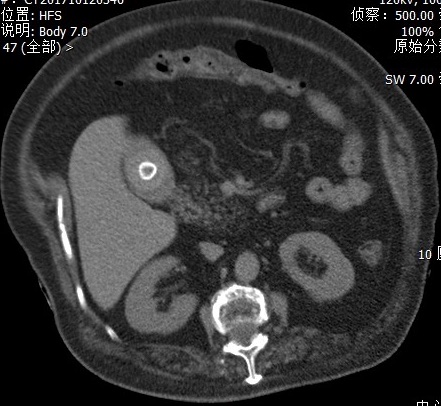

我们赶紧给患者安排了急诊腹部CT,从图片看肝内胆管存在多发积气,胆囊结石的位置与十二指肠关系密切,怀疑结石压穿了胆囊和十二指肠壁形成了内瘘。

急诊CT发现肝内胆管积气